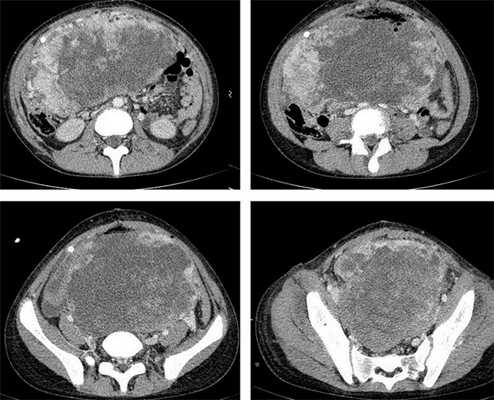

Яичники

Овариальные (расположенные в яичниках, яичниковые) опухоли наиболее часто проявляются болью в животе. При осмотре пальпируется опухоль в малом тазу, часто - в брюшной полости. Также за счет асцита (скопления в брюшной полости жидкости) увеличен живот. Нередко у девочек с таким диагнозом бывает лихорадка.

Самая часто диагностируемая герминогенная опухоль - это дисгерминома. Преимущественно ее обнаруживают во второй декаде жизни. У маленьких девочек встречается редко. Такое заболевания сравнительно быстро распространяется, поражая брюшину и второй яичник. Обычно новообразования односторонние, имеют большие размеры. В связи с этим частое явление - разрыв капсулы новообразования.

Рисунок 3. - тератома яичника а -УЗИ, б — МРТ.

Злокачественные тератомы обычно проявляются неспецифической клинической картиной, которая связана с наличием опухоли:

- увеличенный объем живота;

- боль;

- нарушение менструального цикла (наблюдается не всегда).

Рисунок 8. КТ органов брюшной полости - на снимках вы можете увидеть опухоль яичника.